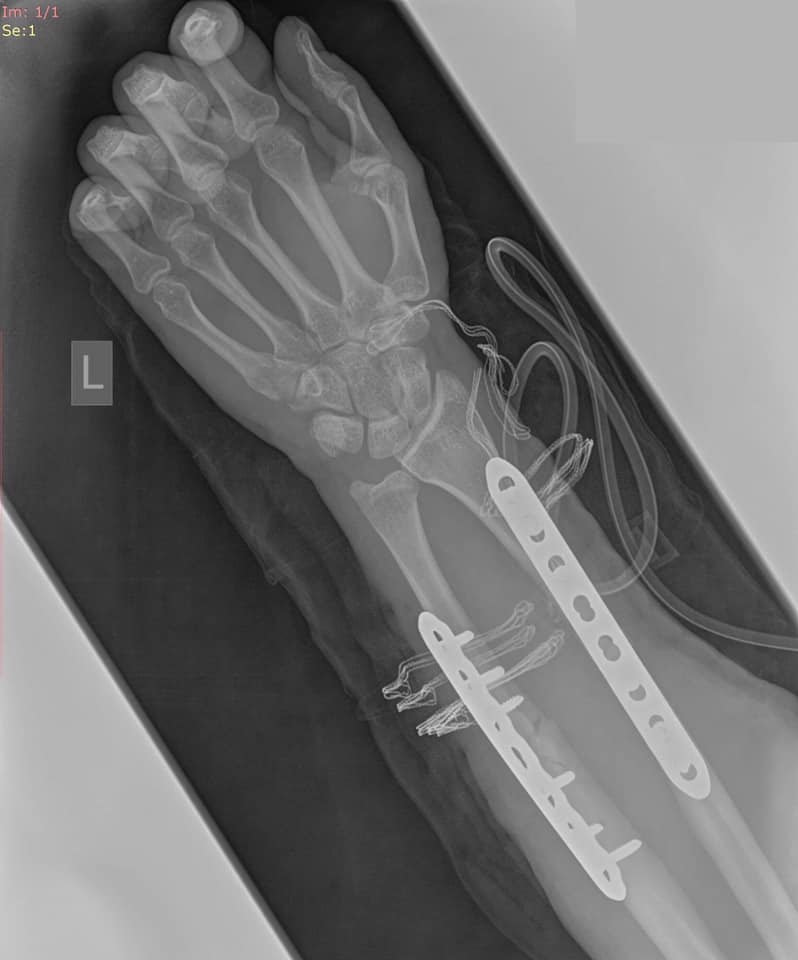

- *złamania kości